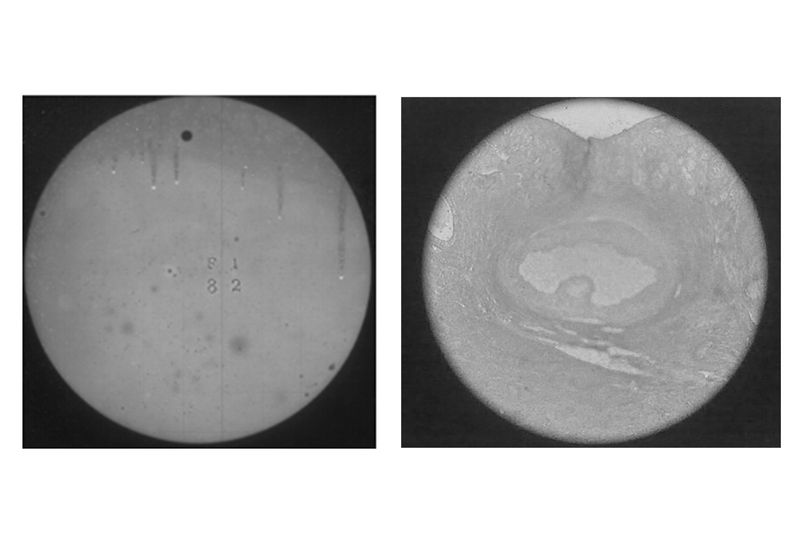

© Xanthe Hutchinson - L: The Transit of Venus R: Histology of an Ovary

i

L: The Transit of Venus R: Histology of an Ovary